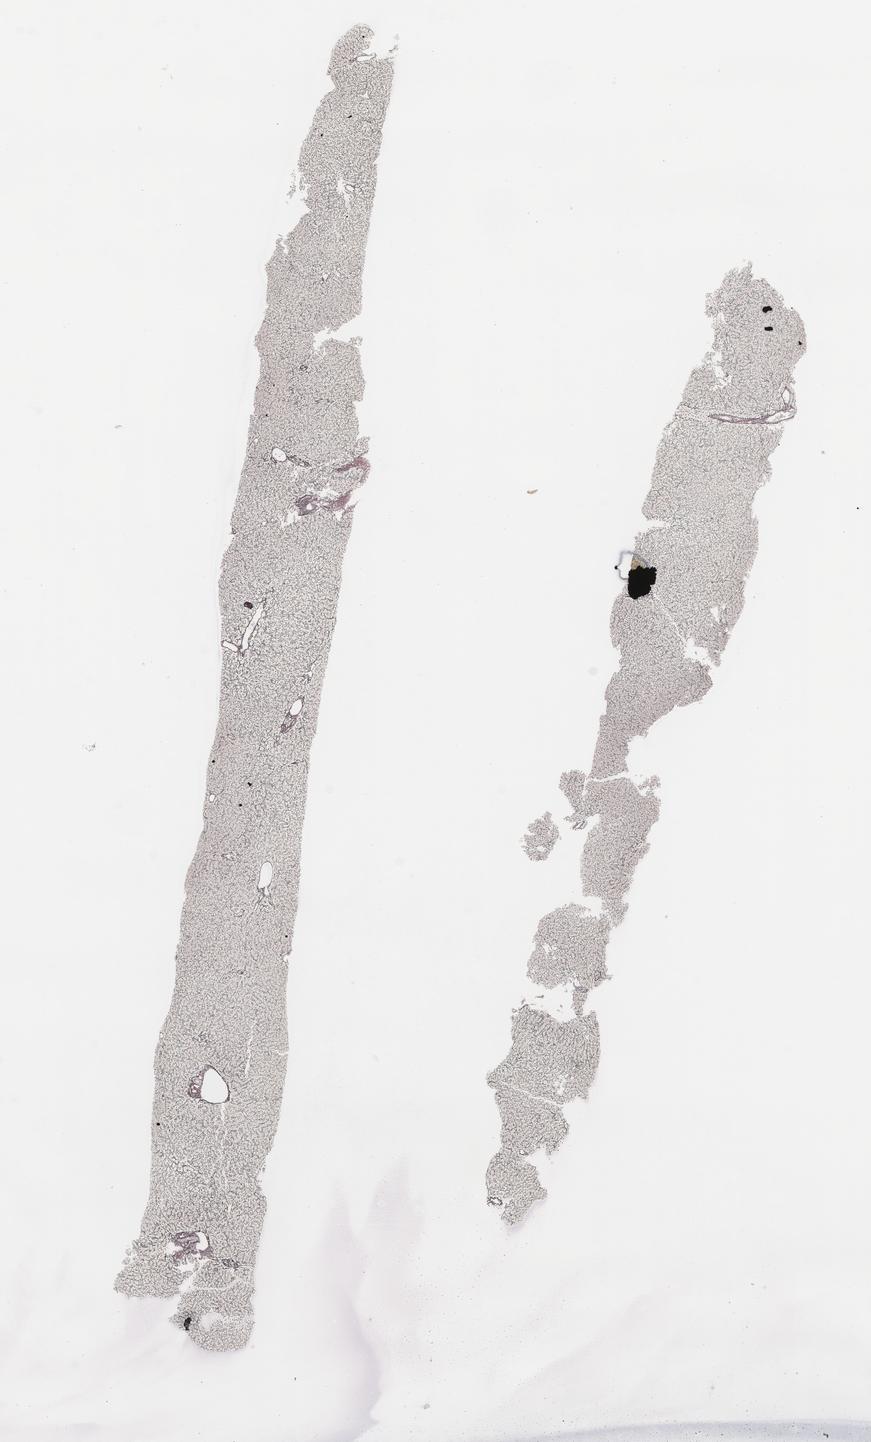

This dataset contains anonymised whole slide images (WSIs) of human liver received during routine clinical practice, comprising a variety of benign and malignant diagnoses. This dataset includes biopsies comprising a mixture of non-targeted/medical and tumour (primary or metastatic) All cases include a H&E stain along with any additional histochemical or immunohistochemical stains where available.

Histopathology |

Resection Fine needle biopsy (FNB) Biopsy (transplant) Biopsy (targeted) Biopsy (non-targeted) |

ZN Tubercle Bacilli Shikata Orcein stain Hepatitis B surface antigen Hematoxylin and Eosin Reticulin Cytokeratin Associated Marker 5.2 Immuno Spare Martius Scarlet Blue Elastic Van Gieson Van Gieson CytoKeratin 7 Epstein-Barr Virus Grocott's Methenamine Silver Immunohistochemical (IHC) staining for CK5D3/CK8/18 Periodic Acid-Schiff Masson's Trichrome Glutamine Synthetase Perls (Iron) Periodic Acid-Schiff with Diastase |

| Number of WSIs | 933 |

| Number of cases | 136 |